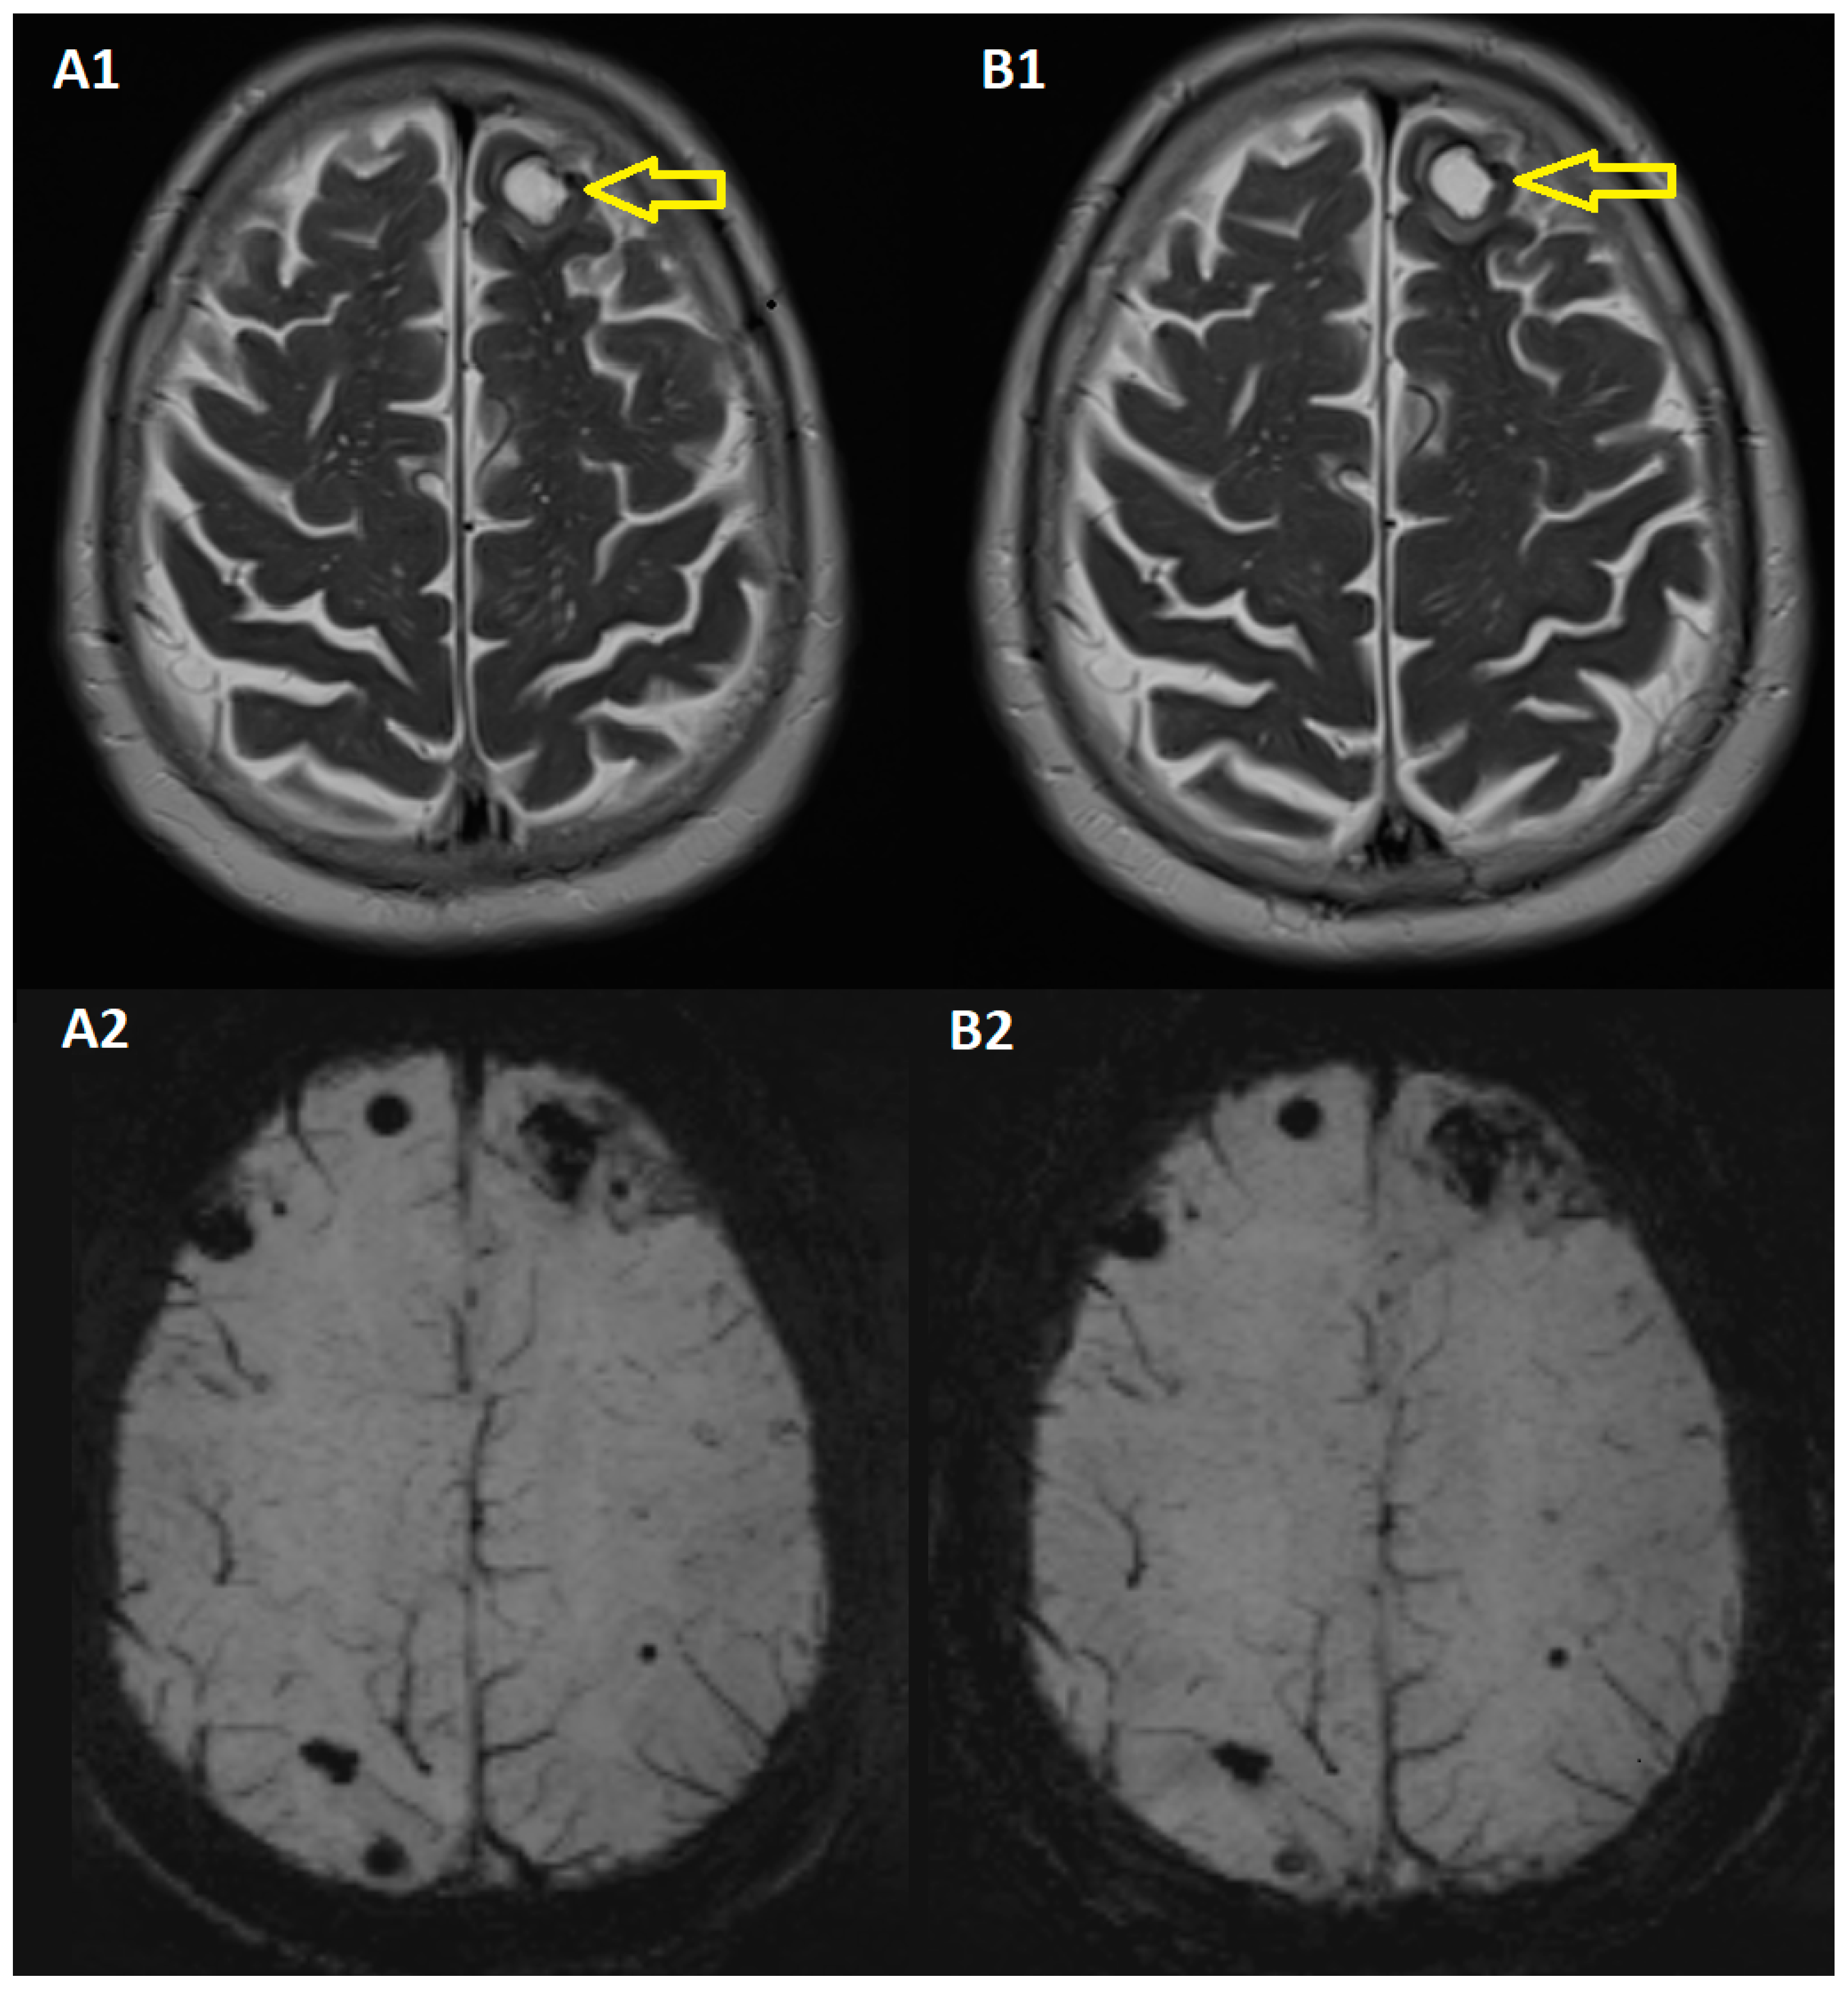

2.1. At the Cerebral Level

- After an initial slight progression at the cerebral level, after radiotherapy, and under immunotherapy, the disease became stable at the cerebral level, and 28 months after the diagnosis of cerebral metastases, in September 2023, a complete remission was recorded.